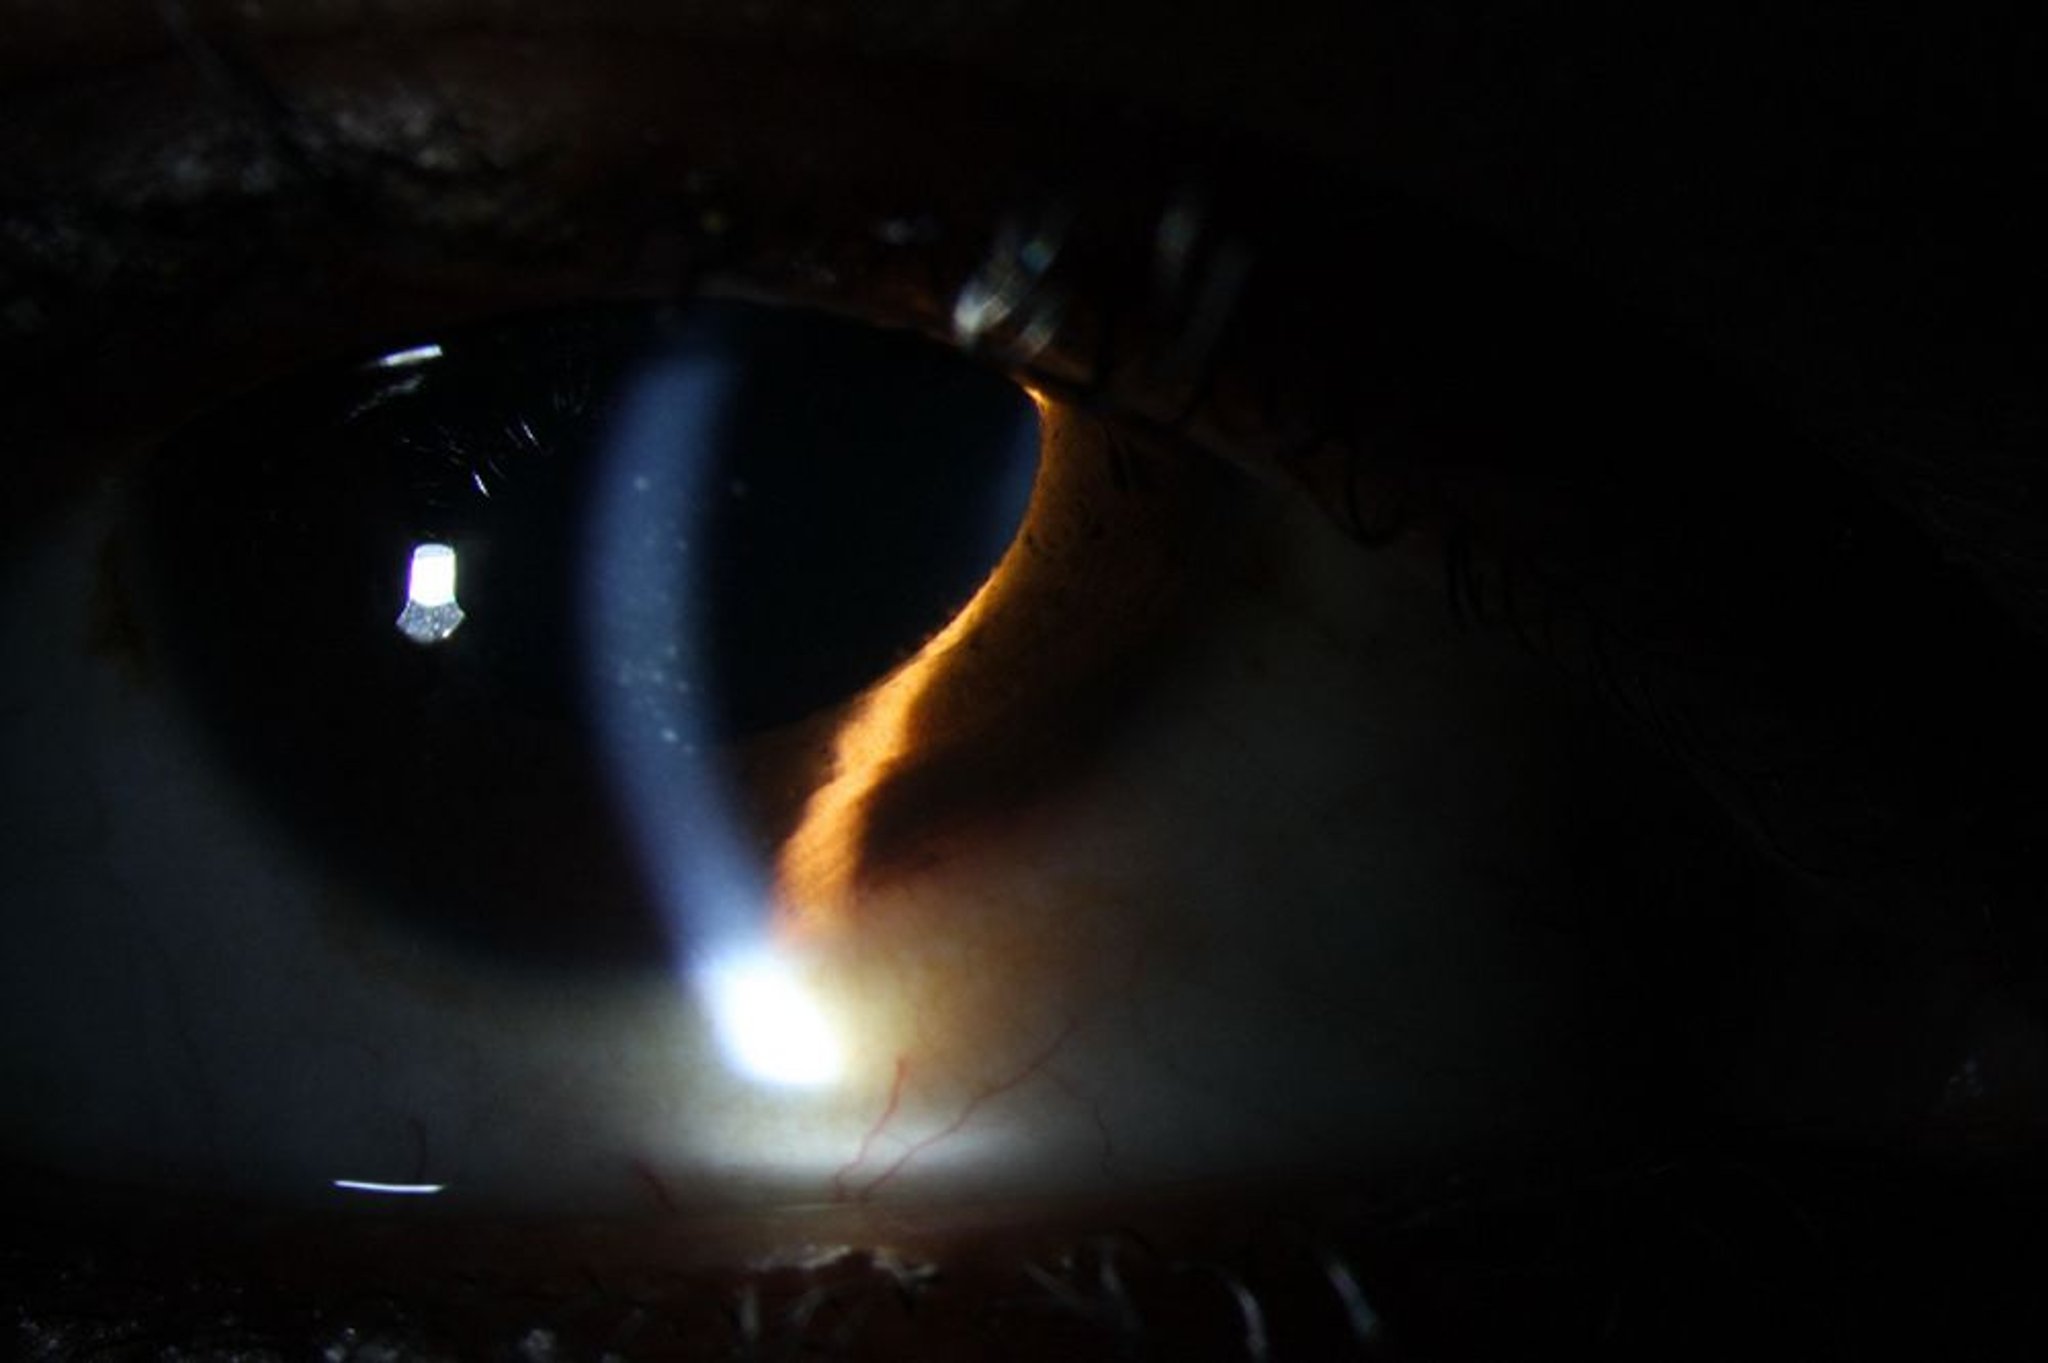

Uveite (anteriore)

L'uveite anteriore può causare arrossamento, precipitati di cheratina sull'endotelio corneale (mostrato), così come i globuli bianchi e la flare (proteine) nella camera anteriore.

Image courtesy of Sunir Garg, MD.